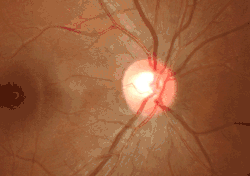

Ophthalmoscopy photograph showing the optic disc as a bright area on the right where blood vessels converge.

The optic disc or optic nerve head is the point of exit for ganglion cell axons leaving the eye. Because there are no rods or cones overlying the optic disc, it corresponds to a small blind spot in each eye.

The ganglion cell axons form the optic nerve after they leave the eye. The optic disc represents the beginning of the optic nerve and is the point where the axons of retinal ganglion cells come together. The optic disc in a normal human eye carries 1–1.2 million afferent nerve fibers from the eye toward the brain. The optic disc is also the entry point for the major arteries that supply the retina with blood, and the exit point for the veins from the retina.[1]